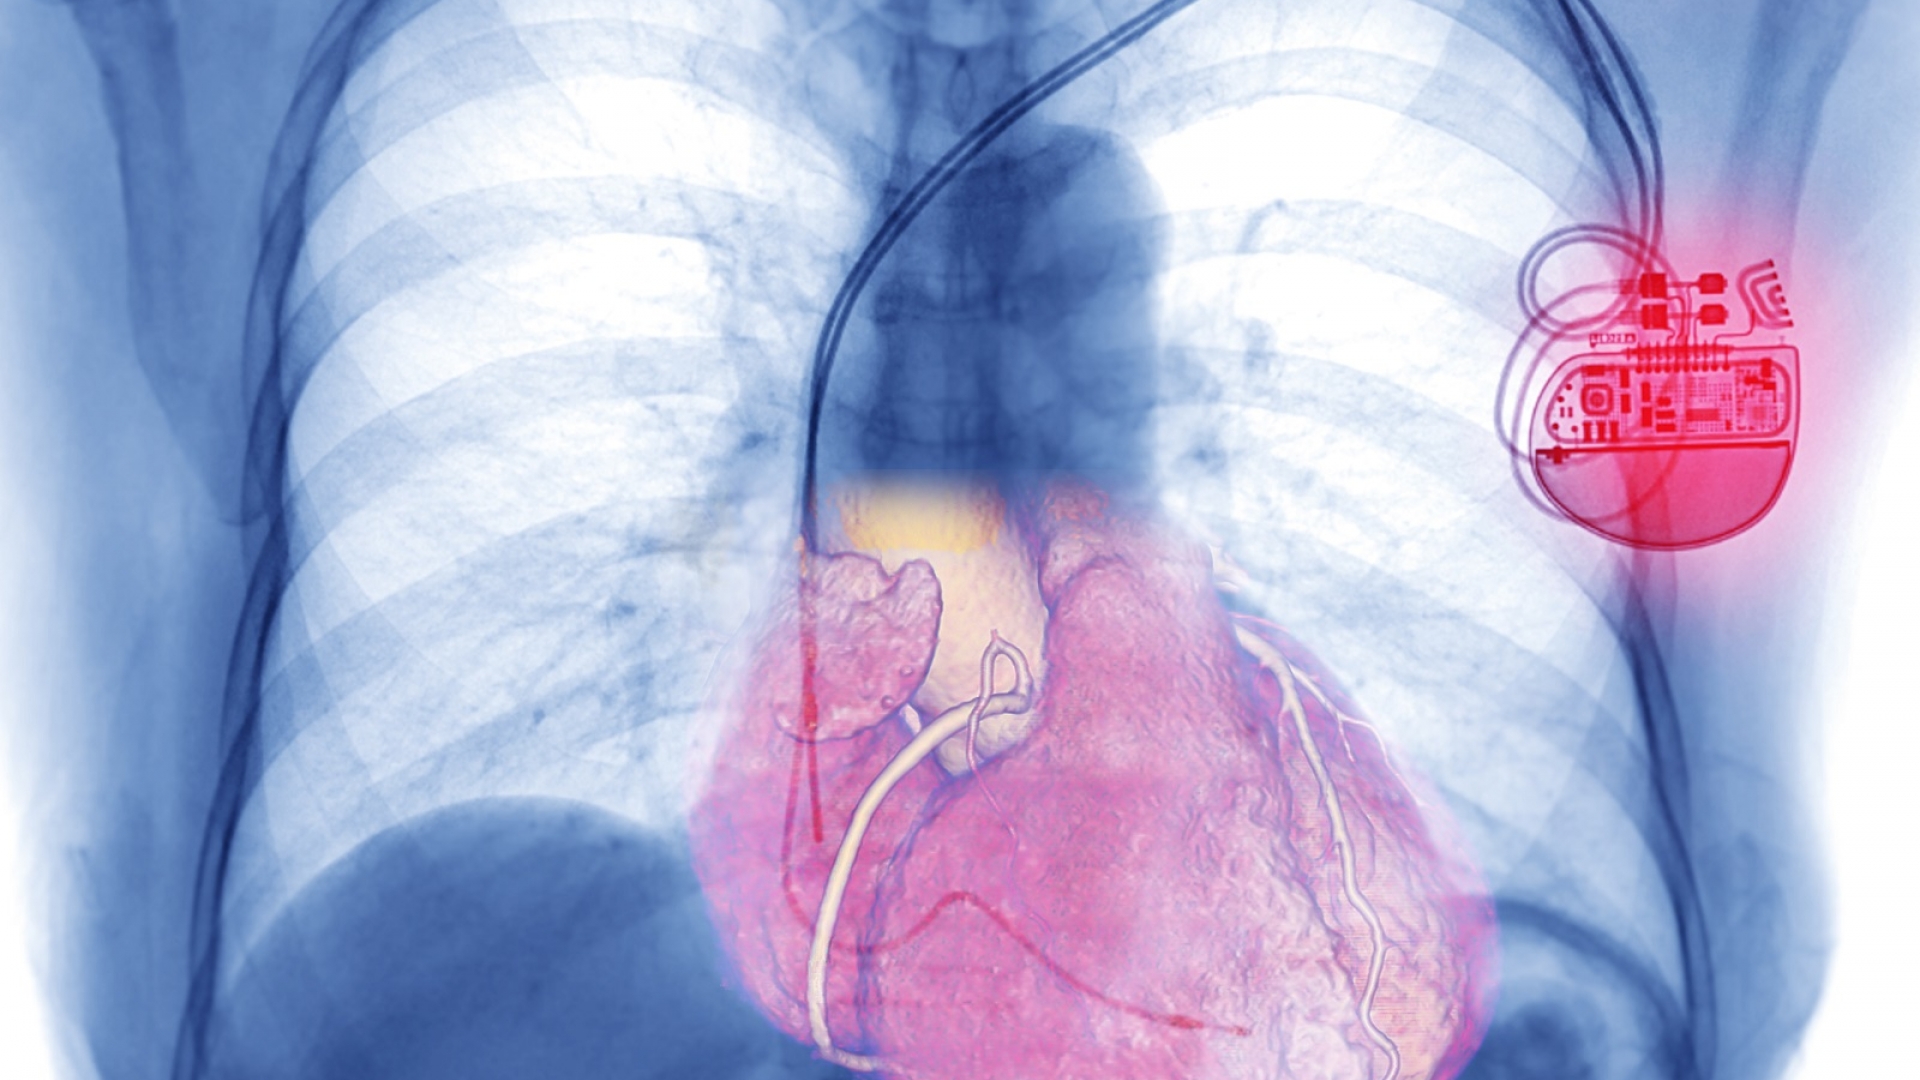

Moderne Herzschrittmacher bestehen aus einem Schrittmacheraggregat und ein bis drei hauchfeinen Sonden. Das Aggregat ist gerade einmal so groß wie zwei aufeinander liegende Zwei-Euro-Münzen und beinhaltet die nötige Technik, um das Herz mit gezielten Stromimpulsen so zu stimulieren, dass es schnell genug schlägt. Diese Impulse gelangen über die Sonden – dünne, kunststoffummantelte Kabel mit Elektroden an der Spitze – bis zum Herzmuskel. Dort geben die Elektroden kurze Stromimpulse, die eine Kontraktion des Herzens auslösen und ihm den Takt vorgeben. Angetrieben wird der Schrittmacher mit einer Lithiumbatterie, die mindestens sieben bis zehn Jahre hält.

An welchen Stellen und mit wie vielen Sonden ein Herz stimuliert werden muss, hängt von der Ursache der Herzrhythmusstörungen ab. Der Herzmuskel besteht aus dem rechten und dem linken Vorhof sowie der rechten und der linken Herzkammer. Normalerweise pumpt das Herz Blut durch den Körper, indem sich zunächst die Vorhöfe und anschließend die Herzkammern synchronisiert zusammenziehen. Die Impulse für die Vorhöfe stammen vom sogenannten Sinusknoten, die für die Herzkammern vom AV-Knoten. Die Probleme liegen in der Regel also bei einem von beiden.

Bei einer Erkrankung des Sinusknotens kommt meist ein sogenannter Einkammer-Schrittmacher zum Einsatz, der entweder den rechten Vorhof oder die rechte Herzkammer mit einer einzelnen Sonde stimuliert. Ein Zweikammer-Schrittmacher besteht aus zwei Sonden, sie sowohl den rechten Vorhof als auch die rechte Kammer stimulieren. Sie kommen bei Problemen mit dem AV-Knoten in Frage. Die seltenste Variante sind Dreikammer-Schrittmacher, bei denen eine dritte Elektrode bis in die linke Herzkammer führt. Sie bieten sich etwa dann an, wenn der Herzmuskel stark geschwächt ist und sich die Herzkammern nicht mehr synchronisiert zusammenziehen können.

Röntgenbild eines Brustkorbs mit Herzschrittmacher

Zweikammerschrittmacher mit Elektroden zur rechten Vorkammer und zur rechten Hauptkammer des Herzes.